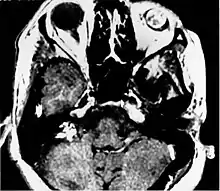

Imaging studies help to identify the tumor and the specific anatomic site of involvement. Magnetic resonance images show a hyperintensity (hypervascularity) of a heterogeneous mass by T1 weighted images. Computed tomography shows a multilocular, lytic destructive temporal bone mass, centered on the vestibular aqueduct (between internal auditory canal and sigmoid sinus).[1][6][7]